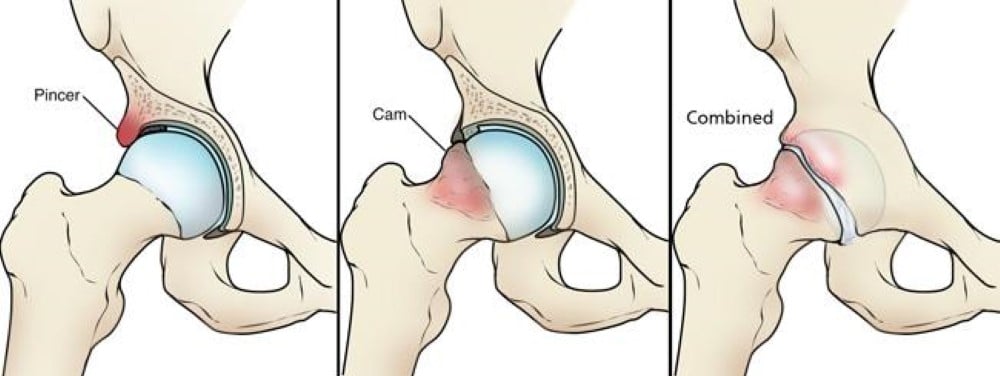

Femoroacetabular Impingement